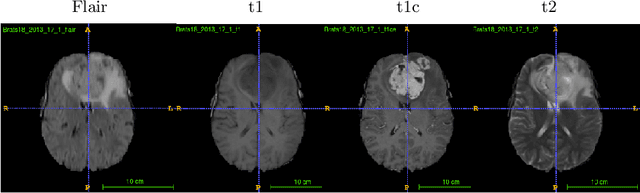

Abstract:In this work, we develop an attention convolutional neural network (CNN) to segment brain tumors from Magnetic Resonance Images (MRI). Further, we predict the survival rate using various machine learning methods. We adopt a 3D UNet architecture and integrate channel and spatial attention with the decoder network to perform segmentation. For survival prediction, we extract some novel radiomic features based on geometry, location, the shape of the segmented tumor and combine them with clinical information to estimate the survival duration for each patient. We also perform extensive experiments to show the effect of each feature for overall survival (OS) prediction. The experimental results infer that radiomic features such as histogram, location, and shape of the necrosis region and clinical features like age are the most critical parameters to estimate the OS.

Abstract:Segmentation of brain tumor from magnetic resonance imaging (MRI) is a vital process to improve diagnosis, treatment planning and to study the difference between subjects with tumor and healthy subjects. In this paper, we exploit a convolutional neural network (CNN) with hypercolumn technique to segment tumor from healthy brain tissue. Hypercolumn is the concatenation of a set of vectors which form by extracting convolutional features from multiple layers. Proposed model integrates batch normalization (BN) approach with hypercolumn. BN layers help to alleviate the internal covariate shift during stochastic gradient descent (SGD) training by zero-mean and unit variance of each mini-batch. Survival Prediction is done by first extracting features(Geometric, Fractal, and Histogram) from the segmented brain tumor data. Then, the number of days of overall survival is predicted by implementing regression on the extracted features using an artificial neural network (ANN). Our model achieves a mean dice score of 89.78%, 82.53% and 76.54% for the whole tumor, tumor core and enhancing tumor respectively in segmentation task and 67.90% in overall survival prediction task with the validation set of BraTS 2018 challenge. It obtains a mean dice accuracy of 87.315%, 77.04% and 70.22% for the whole tumor, tumor core and enhancing tumor respectively in the segmentation task and a 46.80% in overall survival prediction task in the BraTS 2018 test data set.